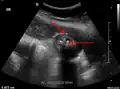

Abdominal ultrasonography showing gallstones, wall thickening and fluid around the gall bladder

Acute cholecystitis as seen on ultrasound. The closed arrow points to gallbladder wall thickening. Open arrow points to stones in the GB

Right upper quadrant abdominal ultrasound is most commonly used to diagnose cholecystitis.[1][26][27] Ultrasound findings suggestive of acute cholecystitis include gallstones, pericholecystic fluid (fluid surrounding the gallbladder), gallbladder wall thickening (wall thickness over 3 mm),[28] dilation of the bile duct, and sonographic Murphy's sign.[13] Given its higher sensitivity, hepatic iminodiacetic acid (HIDA) scan can be used if ultrasound is not diagnostic.[13][14] CT scan may also be used if complications such as perforation or gangrene are suspected.[14]